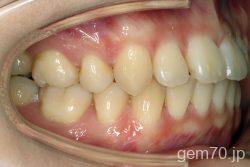

主訴)前歯のかみ合わせが深い

診断)過蓋咬合

年齢)21歳

使用装置)マルチブラケット装置(セラミックブラケット)

治療方法)4|4/4|4

治療期間) 2年8ヵ月 通院回数 32回